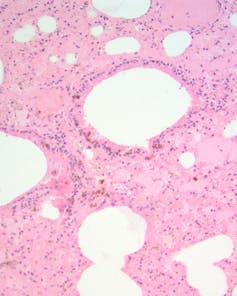

Over the following month, eight more smoky mice died. I inspected the lungs of one – to my shock, it contained thousands of brown smoke particles. Once I knew the distribution of particles to look for, I found them in most of the other dead mice too.

When I and other veterinary pathologists examined organs of the mouse under the microscope, the only abnormality we could find was fluid and congestion in the mouse’s lungs.